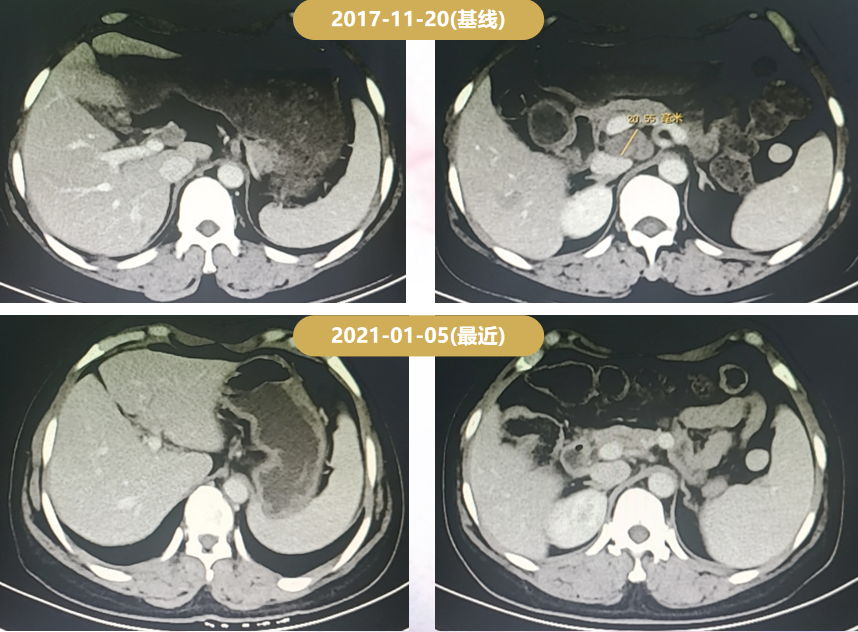

2017-11-20复查增强CT示:腹腔、后腹腔淋巴结肿大,PD出组。

治疗期间每2周期评价一次:最佳疗效为PR;PFS为8.3个月。

Δ一线治疗期间的CT疗效评价

最佳疗效:PR。

Δ二线治疗期间的CT疗效评价

患者为绝经前女性,右乳癌术后,肝转移、骨转移、腹腔淋巴结转移,HR-/HER2+。术后仅接受TEC辅助化疗6周期,DFS为39月;2017-03-10至2017-11-20:曲妥珠单抗+多西他赛6周期序贯曲妥珠单抗靶向治疗6周期,最佳疗效PR,PFS为8.3月;2017-12-07至今接受T-DM1二线治疗(3.6 mg/kg q3w IV),PFS>46个月,患者耐受性良好。